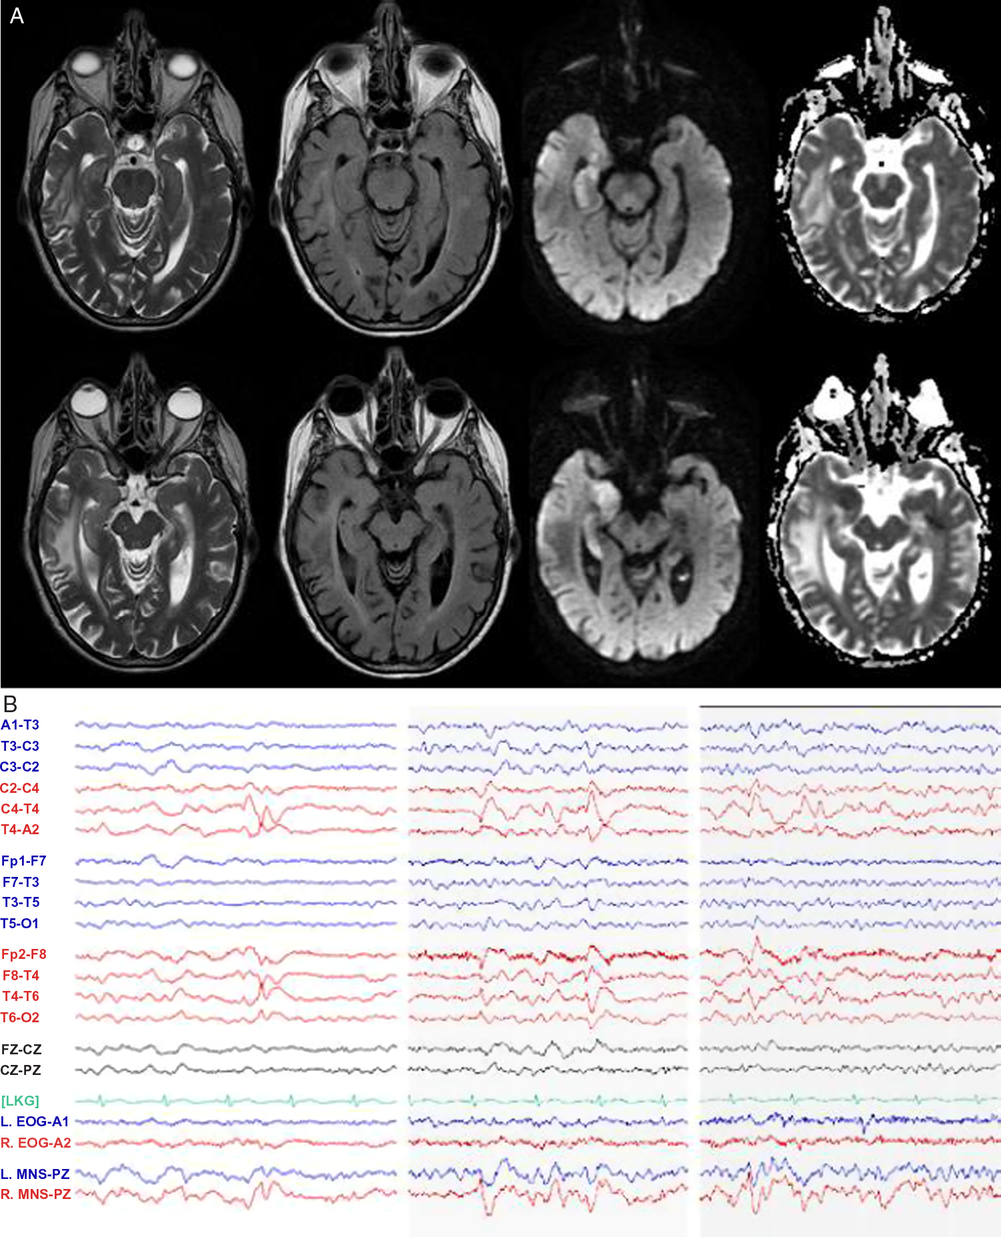

Magnetic resonance imaging (MRI) of the brain (Figure 2A) unexpectedly showed isolated diffusion restriction in the right mesial temporal lobe and electroencephalogram (EEG) revealed right anterior and mid-temporal epileptiform discharges (Figure 2B). The post-test probability of a viral encephalitis had increased, so although the patient remained afebrile and neurologically unchanged; intravenous acyclovir and antiepileptic drug therapy with levetiracetam were initiated, and a lumbar puncture was performed. This showed normal acellular cerebrospinal fluid with both negative cultures and viral polymerase chain reaction (including herpes simplex). Antiviral therapy was discontinued, and the patient remained hemodynamically and neurologically stable on levetiracetam. A thorough work-up for secondary causes of hypertension was pursued in hospital with imaging and laboratory tests excluding endocrinopathy, renal artery stenosis, and pheochromocytoma. The patient was discharged home at her neurologic baseline with a new diagnosis of epilepsy.

Figure 2: MRI and EEG day 2 after presentation. (A) MRI T2-weighted, T2 fluid attenuated inversion recovery (FLAIR), diffusion-weighted imaging (DWI), and apparent diffusion coefficient (ADC) sequences demonstrating right mesial temporal lobe restricted diffusion and (B) EEG demonstrating right anterior and mid-temporal epileptiform discharges at T4 and F8-T4. n.b MNS “mandibular notch surface.”

We report a case highlighting the significant autonomic changes that can accompany temporal lobe seizures, through disruption of the CAN.Reference Baumgartner, Lurger and Leutmezer1, Reference Benarroch4, Reference Mraovitch and Calando5 Clinical studies suggest that these functions are lateralized with right hemispheric ictal activity accompanied by sympathetic excess (e.g. tachyarrhythmia, hypertension), whereas ictal bradyarrhythmia may be more common with left temporal seizures.Reference Baumgartner, Lurger and Leutmezer1, Reference Galli and Lombardi7–Reference Chouchou, Bouet, Pichot, Catenoix, Mauguiere and Jung9 An analogy and memory aid for the right hemisphere “go” and left hemisphere “slow” signal is the configuration of the gas pedal and brake pedal in a car. Additional features, as were present in our case include hypertension and “neurogenic pulmonary edema,” thought to be driven by sympathetic nervous system overactivation in acute central nervous system dysfunction.Reference Devinsky2 Although impossible to definitively rule out other causes of pulmonary edema, we suggest a neurogenic cause given the findings of acute dyspnea, tachypnea, and tachycardia in our patient, accompanied by chest x-ray imaging revealing alveolar opacities with a normal-sized heart, as well as echocardiogram revealing normal systolic ejection fraction. On review by cardiology, the ST segment changes on ECG were considered related to severe hypertension superimposed on coronary artery disease; however, ECG abnormalities can result from insular seizures; as well, cardiac type chest pain has been previously described in seizures involving limbic structures.Reference Baumgartner, Lurger and Leutmezer1, Reference Benarroch4 Urinary urge, as in our case, has previously been described in non-dominant temporal lobe seizures, with single photon emission computed tomography (SPECT) imaging highlighting hyperperfusion of the insula and superior temporal gyrus.Reference Devinsky2, Reference Baumgartner, Gröppel and Leutmezer10 The recurrent viscerosensory spells linked to negative thoughts, revealed in follow-up, coupled with the evidence of encephalomalacia of the posterior insula on CT scan (Figure 1A), suggest that our patient’s focal seizures may have started in the insula with propagation to medial temporal structures, resulting in dysautonomia and the restricted diffusion present on MRI (Figure 2).